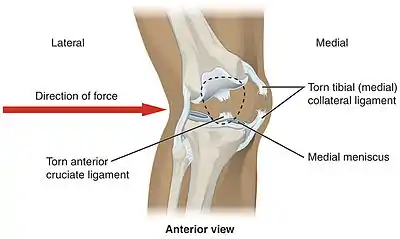

Knee injuries are the second most common injury in netball and are the most serious in regards to cost and disability. Studies show that majority of knee injuries are new injuries, and those who sustain a knee injury often withdraw from participation in netball. The most common knee injuries are meniscal and major ligament sprains/ruptures. The most commonly injured ligament is the Anterior Cruciate Ligament(ACL). The ACL allows a twisting motion at the knee. Common symptoms of an ACL rupture include a “popping” sound at the time of the injury, severe pain, swelling and a feeling of instability. ACL injuries are difficult to effectively diagnose without the assistance of Medical Resonance Imaging (MRI). A ruptured ACL will require knee reconstruction surgery that will result in the athlete being out of the game for 9–12 months.[3]